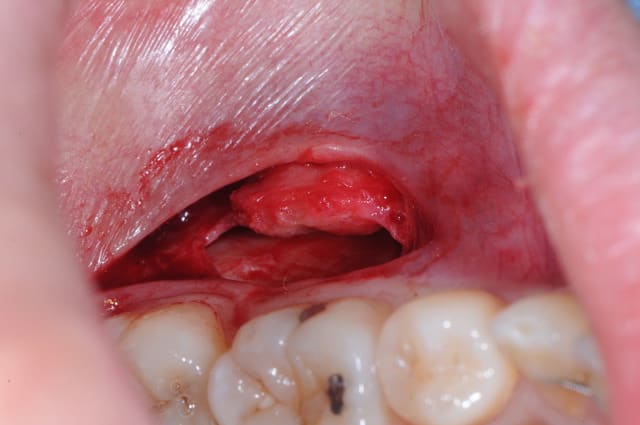

j'ai réalisé une exerèse d'un petit "fibrome" au niveau de la partie muqueuse de la lèvre mandibulaire, avec l'accord du dermato qui a vu les photos.

Dsc 0853 o2u5mi - Eugenol

Dsc 0855 vczury - Eugenol

Dsc 0856 zsy2pv - Eugenol

Dsc 0857 gmhyjs - Eugenol